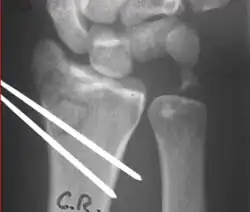

X-rays of pins across a distal radius fracture: Notice the ulnar styloid base fracture, which has not been fixed. This patient has instability of the DRUJ because the TFCC is not in continuity with the ulna.

Surgery is generally indicated for displaced or unstable fractures.[18] The techniques of surgical management include open reduction internal fixation (ORIF), external fixation, percutaneous pinning, or some combination of the above. The choice of operative treatment is often determined by the type of fracture, which can be categorized broadly into three groups: partial articular fractures, displaced articular fractures, and metaphyseal unstable extra- or minimal articular fractures.[5]

Surgical options have been shown to be successful in patients with unstable extra-articular or minimal articular distal radius fractures. These options include percutaneous pinning, external fixation, and ORIF using plating. Patients with low functional demand of their wrists can be treated successfully with nonsurgical management; however, in more active and fit patients with fractures that are reducible by closed means, nonbridging external fixation is preferred, as it has less serious complications when compared to other surgical options.[5] The most common complication associated with nonbridging external fixation is pin tract infection, which can be managed with antibiotics and frequent dressing changes, and rarely results in reoperation.[5] The external fixator is placed for 5 to 6 weeks and can be removed in an outpatient setting.[5]

These fractures, although less common, often require surgery in active, healthy patients to address displacement of both the joint and the metaphysis. The two mainstays of treatment are bridging external fixation or ORIF. If reduction can be achieved by closed/percutaneous reduction, then open reduction can generally be avoided. Percutaneous pinning is preferred to plating due to similar clinical and radiological outcomes, as well as lower costs, when compared to plating, despite increased risk of superficial infections.[24] Level of joint restoration, as opposed to surgical technique, has been found to be a better indicator of functional outcomes.[5]